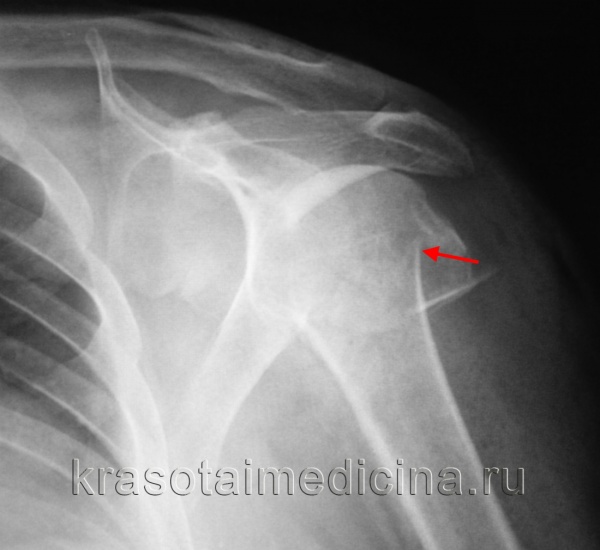

Перелом шейки плеча ( Перелом шейки плечевой кости )

Перелом шейки плеча – это нарушение целостности плечевой кости в ее верхней части, чуть ниже плечевого сустава. Чаще возникает у женщин пожилого и старческого возраста, причиной становится падение на отведенную назад или прижатую к туловищу руку. Проявляется болями, отеком и ограничением движений в плечевом суставе. Иногда определяется костный хруст. Для уточнения диагноза проводят рентгенологическое исследование. Лечение обычно консервативное: анестезия, репозиция и иммобилизация. При невозможности сопоставления фрагментов выполняют операцию.

Симптомы перелома

Пациенты с вколоченными переломами шейки плеча предъявляют жалобы на умеренную боль в области сустава, усиливающуюся при движениях. Сустав отечен, нередко обнаруживаются кровоизлияния. Активные движения возможны, но ограничены из-за боли. Пальпация головки плеча болезненна. При переломах со смещением симптомы выражены более ярко: нарушается округлая форма сустава, заметно некоторое выстояние акромиального отростка и западение в области головки.

Отмечается изменение оси плеча: она проходит косо, при этом центральный конец оси направлен вперед и внутрь. Локоть смещен кзади и отстоит от туловища, однако фиксация локтевого сустава (как при вывихе) отсутствует, симптом пружинящего сопротивления не выявляется. Определяется укорочение больного плеча на 1-2 см. Активные движения невозможны, пассивные резко ограничены из-за боли и иногда сопровождаются костным хрустом. При вращательных движениях головка не перемещается вместе с плечевой костью.

При пальпации хирургической шейки возникает резкая локальная болезненность. У худощавых пациентов со слабо развитыми мышцами в подмышечной впадине удается пальпировать конец дистального фрагмента кости. В отдельных случаях сместившийся отломок может сдавливать сосудисто-нервный пучок, что проявляется синюшностью из-за нарушения венозного оттока, отечностью конечности и ощущением ползающих мурашек.

Для уточнения диагноза назначают рентгенографию плечевого сустава в двух проекциях: прямой и «эполетной» (аксиальной). «Эполетный» снимок выполняют, отводя плечо от туловища под углом 30-40 градусов. Большее отведение категорически не рекомендуется, поскольку может усугубить смещение отломков. В сомнительных случаях используют КТ плечевого сустава. При подозрении на сдавление сосудисто-нервного пучка пациентов направляют на консультацию к неврологам или нейрохирургам и сосудистым хирургам.